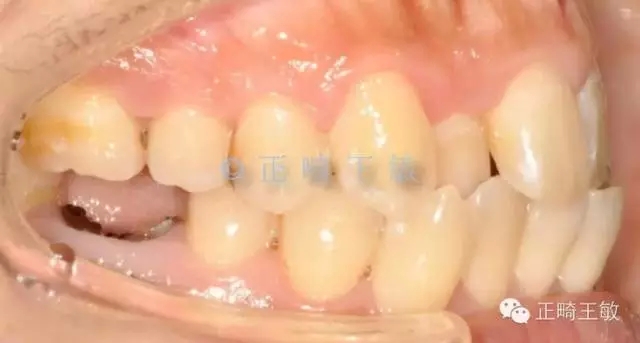

有了一個目標后,矯正就很簡單了,拔掉一顆牙,7個月順利讓牙齒移動到我們想要的位置:

38.webp.jpg

雖然這個時候正畸并沒有結束,但對于種植來說,間隙和排列,已經足夠了,畢竟種植周期也要4個月,后面的治療就是繼續(xù)關閉間隙,調整咬合,同時等著那顆種植牙生根發(fā)芽。來看看最終的樣子:

39.webp.jpg

一年后復查,沒有任何問題。

只拔了一顆小牙,解決了大問題。